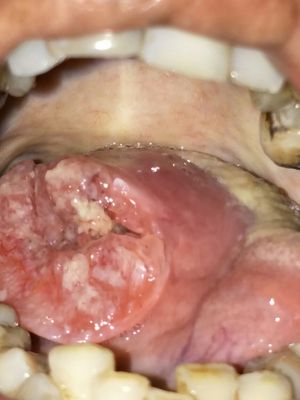

Squamous cell carcinoma of lateral border of tongue